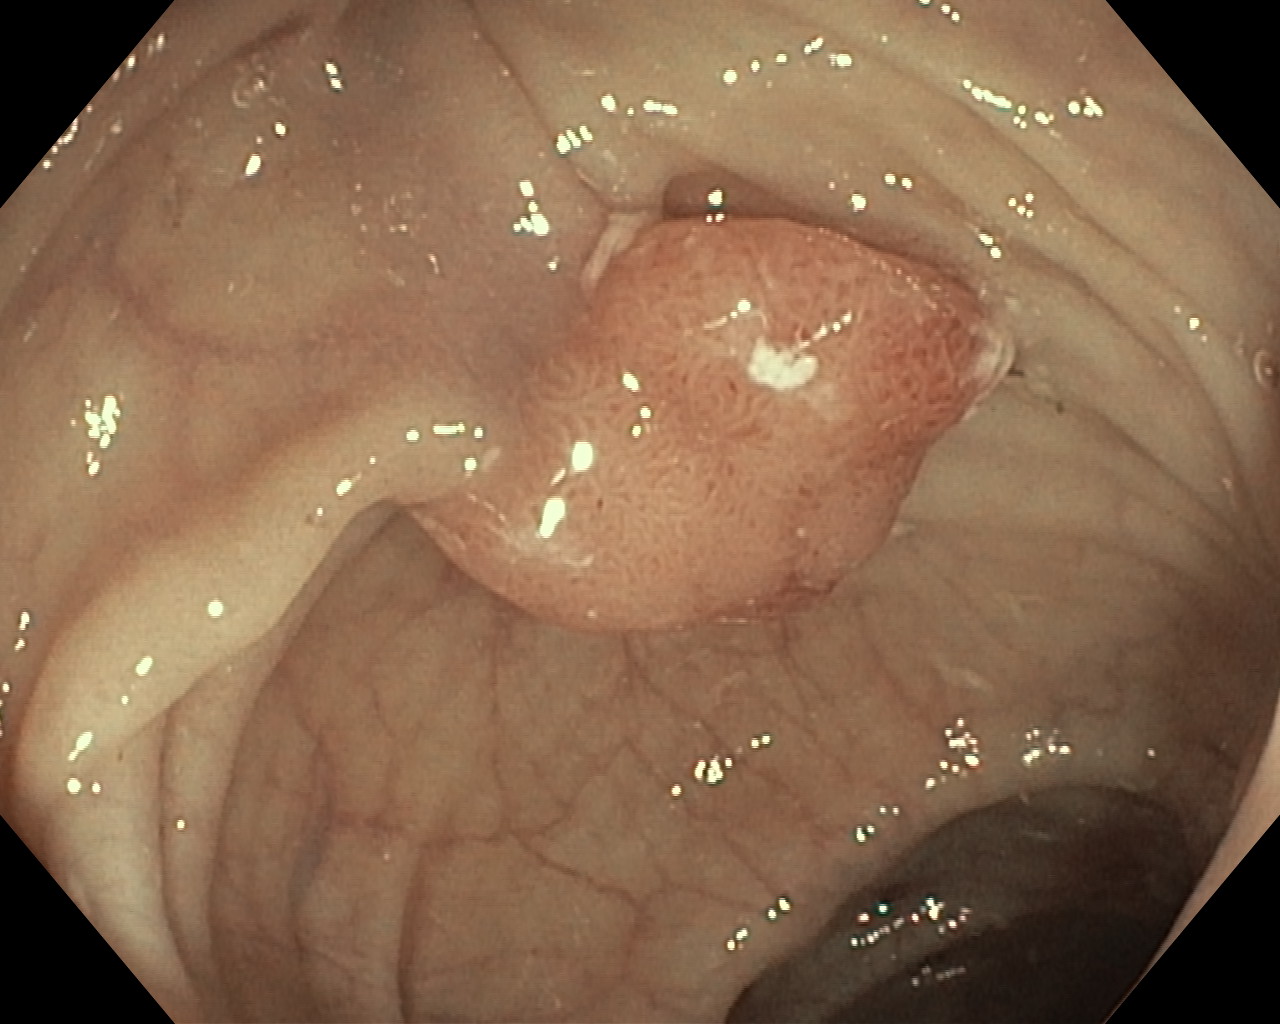

Polipy